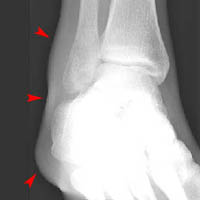

Look at the following radiographs showing swelling (arrows) around the lateral malleolus. Can you see a fracture?

AP view of right ankle